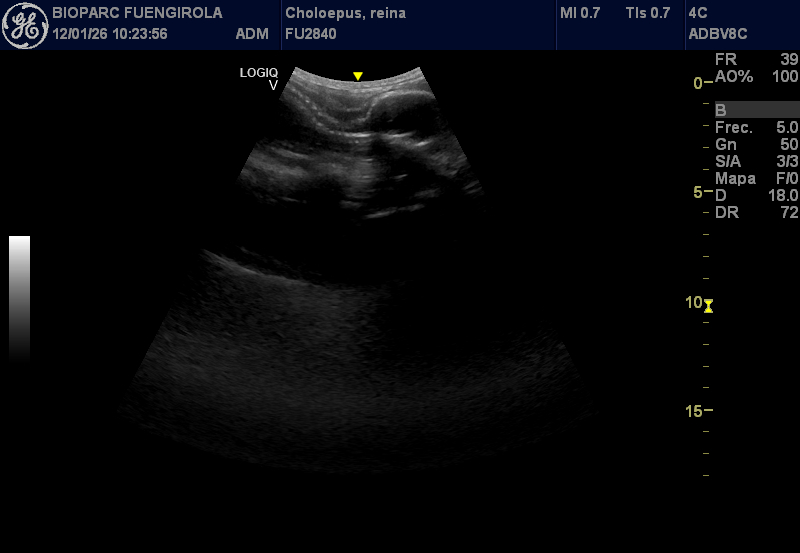

El seguimiento de la gestación se está realizando dentro de los protocolos habituales de cuidado y bienestar del animal, integrando revisiones veterinarias voluntarias y sin ningún tipo de riesgo. Entre ellas se incluyen ecografías realizadas como parte de su rutina diaria, posibles gracias a un avanzado programa de entrenamiento veterinario desarrollado por los equipos de Zoología y Veterinaria de BIOPARC Fuengirola.

Gracias a un proceso progresivo de desensibilización y familiarización, los cuidadores han logrado que Reina acepte de forma natural la presencia del equipo veterinario y el contacto necesario para la exploración abdominal. Para ello, se han simulado previamente las condiciones reales del procedimiento mediante el uso de instrumentos similares a la sonda ecográfica, presiones controladas y la aplicación de geles, siempre sin contacto protegido y bajo estrictas medidas de seguridad. Este trabajo permite monitorizar de forma regular el desarrollo fetal, la frecuencia cardiaca y el estado general de la madre sin alterar su comportamiento.

El embarazo comenzó a sospecharse tras el registro detallado de las cópulas y la posterior observación de una leve distensión abdominal en los últimos meses, apenas perceptible para ojos no expertos. Esta discreción no es casual: se trata de una adaptación evolutiva que permite a los perezosos pasar desapercibidos frente a depredadores como grandes rapaces, felinos o serpientes constrictoras. Los controles veterinarios confirman que el feto se desarrolla con normalidad y a buen ritmo, mientras que Reina mantiene una conducta, alimentación y rutina completamente estables.

El periodo de gestación de esta especie es especialmente largo, con una media estimada de entre 330 y 350 días, aunque existen importantes variaciones descritas en la literatura científica. En estos momentos, los especialistas sitúan a Reina en el último tercio del embarazo, una fase clave que se afronta con un seguimiento continuo y adaptado a sus necesidades.